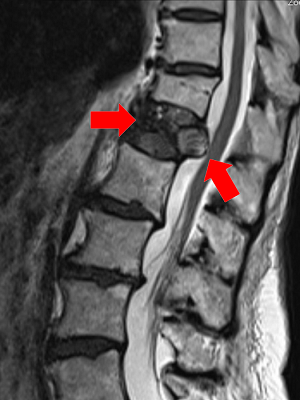

Podstawą diagnostyki złamań kręgosłupa są badania radiologiczne, głównie tomografia komputerowa, która pozwala określić typ złamania. Standardowo wykonuje się także zdjęcie rentgenowskie. Badania rozszerza się często o rezonans magnetyczny, który pozwala zdiagnozować ewentualne uszkodzenie rdzenia kręgowego, krążków międzykręgowych i więzadeł międzywyrostkowych.

Zdjęcie RTG – złamanie niskoenergetyczne z przemieszczeniem do kanału kręgowego